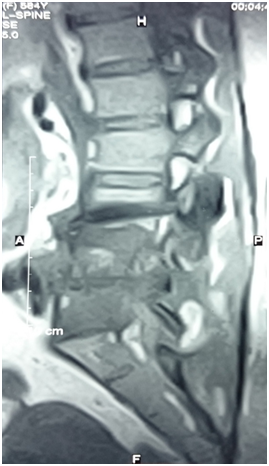

As patient still having backache, Magnetic Resonance Imaging (MRI) lumbo-sacral region was done to evaluate any deterioration in the disc prolapse state. Paraspinal mass was illustrated in MRI assessment (Figure 1) suggestive of metastatic lesion. So, bone scan was ordered to evaluate the nature of the lesion, and the results revealed neoplastic lesion involving L4 (Figure 2).

Figure 2 Bone scan, focal area of intense radioactive tracer uptake is seen the right pedicle of 4th lumbar spine?? Metastatic lesion otherwise the remained of scanned skeleton is free.